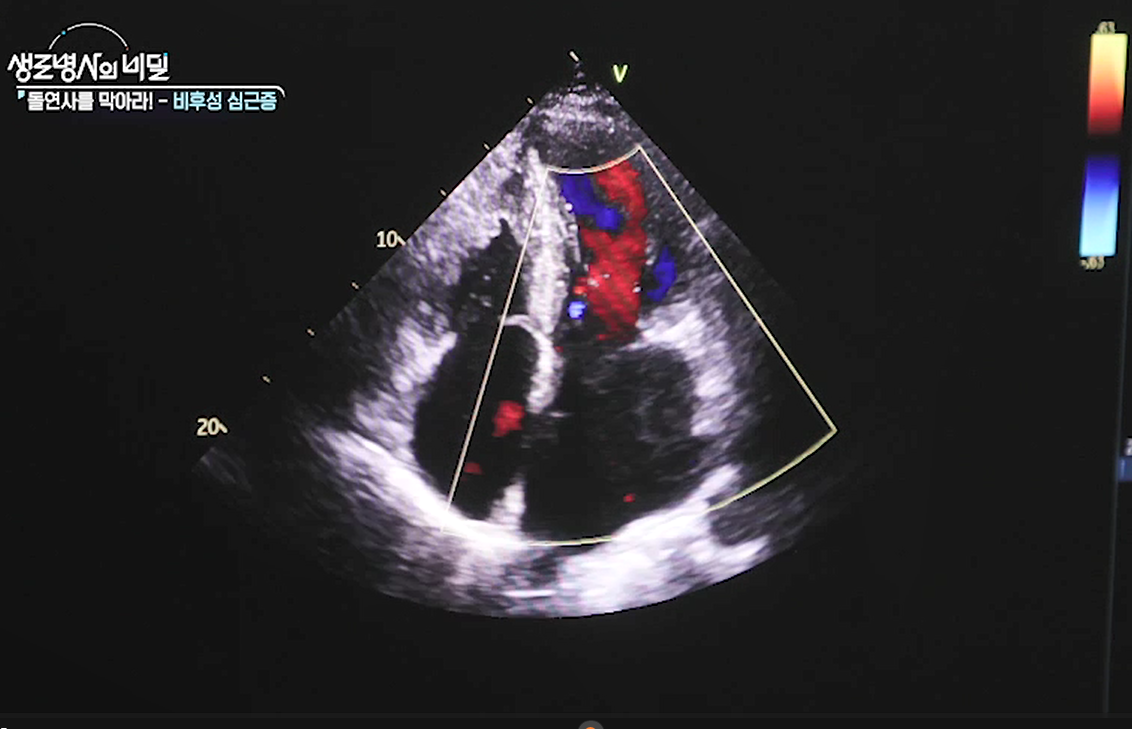

그의 일상을 무너뜨린 질환은 비후성 심근증. 특히 그의 심장은 두꺼워진 심근으로 인해 좌심실에서 대동맥으로 혈액이 뻗어나가는 길목인 좌심실 유출로가 좁아져 통증을 유발하고 있었다. 좌심실 유출로가 좁아져 심각한 증상을 유발하는 비후성 심근증을 폐쇄성 비후성 심근증으로 부르는데, 일부 폐쇄성 환자들은 수술 치료로 증상을 완화할 수 있다.

두꺼워진 심장은 왜 뇌졸중, 심부전 나아가 돌연사와 같은 심각한 합병증을 부르는가?